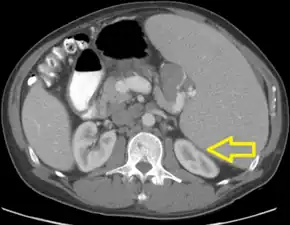

TLS should be suspected in patients with large tumor burden who develop acute kidney failure along with hyperuricemia (> 15 mg/dL) or hyperphosphatemia (> 8 mg/dL). (Most other acute kidney failure occurs with uric acid < 12 mg/dL and phosphate < 6 mg/dL). Acute uric acid nephropathy is associated with little or no urine output. The urinalysis may show uric acid crystals or amorphous urates. The hypersecretion of uric acid can be detected with a high urine uric acid - creatinine ratio > 1.0, compared to a value of 0.6–0.7 for most other causes of acute kidney failure.